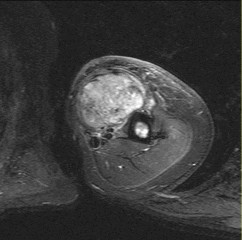

This patient has a dedifferentiated liposarcoma within a preexisting atypical lipomatous tumor. The imaging demonstrates a large fatty mass with increased internal septations proximally (the atypical lipomatous tumor) and a solid enhancing mass distally (the dedifferentiated portion). A biopsy reveals a high-grade liposarcoma. The other diagnostic responses do not reflect sarcomatous transformation of the lesion.

Surgical treatment of a high-grade sarcoma involves wide surgical resection. Radiation decreases local recurrence but does not clearly influence overall survival. The role of chemotherapy in high-grade soft-tissue sarcomas remains investigational; there is a modest (8%-15%) associated improvement in overall survival.

Intramuscular lipomas and atypical lipomatous tumors are treated with marginal resection alone. Radiation therapy for soft-tissue sarcomas may be given before or after surgery. When administered before surgery, patients have a higher wound complication rate but better long-term function attributable to lower rates of lymphedema, fibrosis, and contractures.